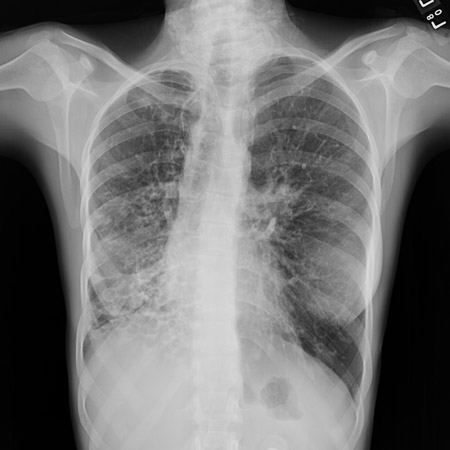

Chest x-ray

A chest x-ray should be obtained early in the evaluation of chronic cough.[38] Although it is not diagnostic of the most common causes, findings may quickly divert the evaluation to causes of greater gravity, such as structural lung diseases. These include lung cancer, pulmonary fibrosis, tuberculosis, bronchiectasis, pneumonia, aspiration, and sarcoidosis.[Figure caption and citation for the preceding image starts]: Chest x-ray showing hyperinflation in a patient with COPD. The hyperinflation is caused by the emphysema component of COPD, rather than the chronic bronchitis that underlies symptoms of coughFrom the personal collection of Dr M. A. Sharifabadand, SUNY at Stony Brook School of Medicine, Department of Pulmonary and Critical Care Medicine, Mineola, New York and Dr J. P. Parsons, The Ohio State University Medical Center, Columbus; used with permission [Citation ends].com.bmj.content.model.assessment.Caption@65a65855[Figure caption and citation for the preceding image starts]: Chest x-ray showing multiple miliary lung metastases (arrows). The primary tumour was a thyroid carcinomaE. Dick, Student BMJ. 2001;9:10-12 [Citation ends].com.bmj.content.model.assessment.Caption@25657fee[Figure caption and citation for the preceding image starts]: Chest x-ray showing left hilar carcinoma (arrow)From: E. Dick, Student BMJ. 2000;8:358-360 [Citation ends].com.bmj.content.model.assessment.Caption@567b9fef[Figure caption and citation for the preceding image starts]: Chest x-ray showing a cavitating right hilar carcinoma (arrow)E. Dick, Student BMJ. 2001;9:10-12 [Citation ends].com.bmj.content.model.assessment.Caption@3d6fa55[Figure caption and citation for the preceding image starts]: Chest x-ray in a patient with bronchogenic carcinoma showing a left-sided pleural effusionFrom: R. Thakkar, Student BMJ. 2001;9:458 [Citation ends].com.bmj.content.model.assessment.Caption@5b46acec[Figure caption and citation for the preceding image starts]: Chest x-ray showing interstitial fibrosis in a patient with amiodarone pulmonary toxicityFrom the personal collection of Dr A. Pataka and Professor P. Argyropoulou, Aristotle University, Thessaloniki, Greece; used with permission [Citation ends].com.bmj.content.model.assessment.Caption@2c3c94b0[Figure caption and citation for the preceding image starts]: Chest x-ray showing pulmonary tuberculosis with cavitationFrom the personal collection of Dr M. Narita, Department of Pulmonary and Critical Care Medicine, University of Washington [Citation ends].com.bmj.content.model.assessment.Caption@3dd7f84b[Figure caption and citation for the preceding image starts]: Chest x-ray showing multiple discrete nodules throughout both lungs (one of which is circled) in a patient with miliary tuberculosisE. Dick, Student BMJ. 2001;9:10-12 [Citation ends].com.bmj.content.model.assessment.Caption@23fa6365[Figure caption and citation for the preceding image starts]: Chest x-ray with lack of normal tapering producing a tram line in a patient with bronchiectasisFrom the personal collection of Dr S.M. Bhorade, University of Chicago Medical Center; used with permission [Citation ends].com.bmj.content.model.assessment.Caption@36b415f2[Figure caption and citation for the preceding image starts]: Chest x-ray with dilated and thickened airways in a patient with bronchiectasisFrom the personal collection of Dr S.M. Bhorade, University of Chicago Medical Center; used with permission [Citation ends].com.bmj.content.model.assessment.Caption@78e208fa[Figure caption and citation for the preceding image starts]: Chest x-ray showing increased opacification of the right perihilar region and superior segment of the right lower and upper lobes consistent with worsening aspiration pneumoniaFrom the personal collection of Dr R. Kanner, University of Utah School of Medicine [Citation ends].com.bmj.content.model.assessment.Caption@71be2c1f[Figure caption and citation for the preceding image starts]: Portable chest x-ray with bibasilar opacities, worse on the right than the left, in a patient with hospital-acquired pneumoniaFrom the personal collection of Dr F. W. Arnold, Division of Infectious Diseases, Department of Medicine, University of Louisville School of Medicine [Citation ends].com.bmj.content.model.assessment.Caption@2c704497[Figure caption and citation for the preceding image starts]: Chest x-ray showing early ill-defined opacities of the right upper lobe above the minor fissure consistent with early changes of aspiration pneumoniaFrom the personal collection of Dr R. Kanner, University of Utah School of Medicine [Citation ends].com.bmj.content.model.assessment.Caption@23fa54d0[Figure caption and citation for the preceding image starts]: A. Portable upright chest x-ray before aspiration; B. Chest x-ray 1 hour after aspiration, showing bilateral diffuse alveolar infiltrates, worse at the bases on the right sideFrom the personal collection of Dr S. Murgu and Dr H. Colt, University of California at Irvine Medical Center [Citation ends].com.bmj.content.model.assessment.Caption@7860be3a[Figure caption and citation for the preceding image starts]: Chest x-ray showing bilateral hilar adenopathy in a patient with sarcoidosisFrom the personal collection of Dr M.P. Muthiah, Division of Pulmonary and Critical Care and Sleep Medicine, University of Tennessee [Citation ends].com.bmj.content.model.assessment.Caption@31e94b4e